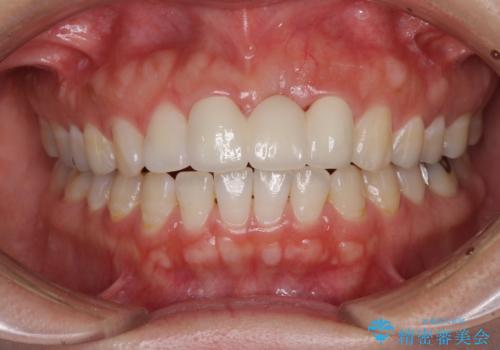

- 接着タイプの前歯のブリッジが不自然であるとのことで来院された患者様です。

欠損部の歯肉が窪んでいるため、歯肉移植により形態を改善し、オールセラミックブリッジにて補綴することとしました。

事前に装着されていた接着タイプのブリッジは、歯の切削量が少ない反面、接着界面から虫歯が進行しやすく、脱落リスクが高くなるというデメリットがあります。